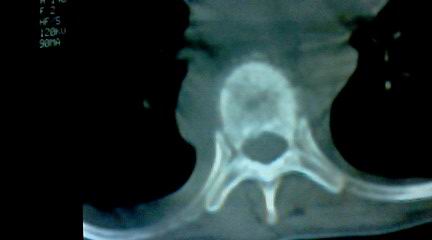

标题: CT25218:请教!胸部CT,胸8椎体骨质破坏,伴周围软组织肿。 [打印本页]

标题: CT25218:请教!胸部CT,胸8椎体骨质破坏,伴周围软组织肿。

患者,女41岁,肢体乏力。

考虑胸椎结核

两肺上叶继发性肺结核;胸椎结核并椎旁寒性脓肿形成。

胸椎结核并椎旁寒性脓肿形成。

恶性,椎体淋巴瘤或pnet并肺内转移。